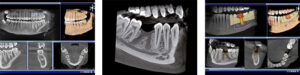

We proudly use the ORTHOPHOS XG 3D, the most popular and leading edge 3D x-ray unit in the world. This amazing technology allows our dental professionals to capture a highly detailed image of your entire jaw in just a single scan – resulting in a quicker diagnosis and reduced exposure to radiation.

If you require prosthetic or surgical dental implants, you can trust Colina Dental to provide you with long-lasting results. By utilizing our cutting-edge 3D technology, we can achieve extreme precision in the planning and placement of your dental implants – leaving you with the most natural looking, beautiful smile.